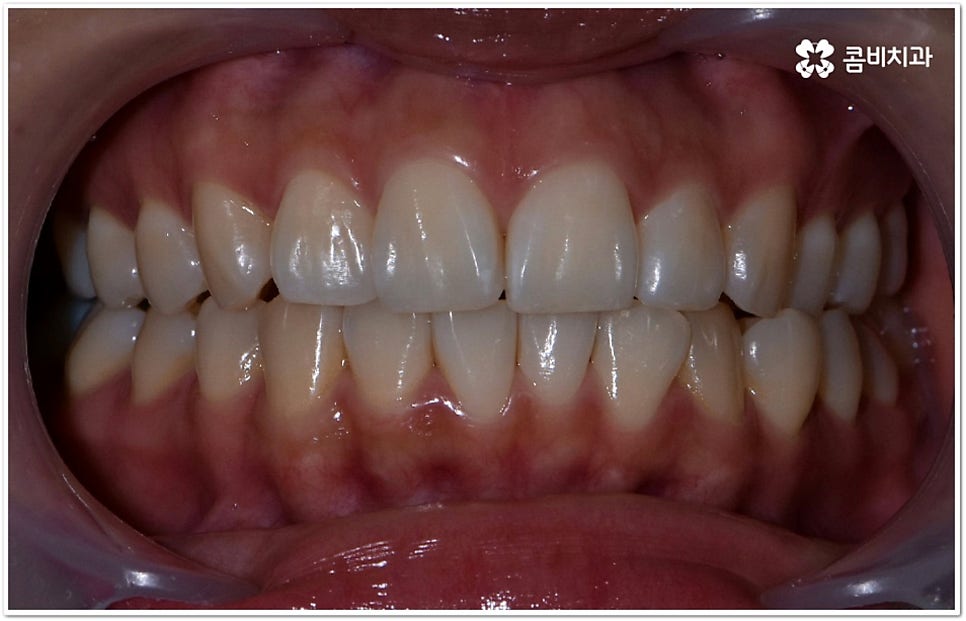

사실 치아가 많이 겹쳐서 삐뚤빼뚤하면 보기에도 좋지 않고 사이사이에 음식물 찌꺼기가 끼어서 충치 같은 구강 질환도 더 자주 발생할 수 있기 때문에 환자분들의 입장에서도 교정 치료를 고려하시는 경우가 많지만, 아주 살짝 덧니가 있을 때는 교정에 대해서 별로 심각하게 생각하지 않으실 수도 있는데요. 이런 덧니는 사람에 따라 오히려 매력 포인트가 될 수도 있기 때문에 스스로 느끼기에 문제가 아니라고 생각한다면 반드시 교정 치료를 해야 하는 것은 아니지만, 만약 입을 벌렸을때 잘 보이는 앞니, 송곳니 등이 덧니라서 웃거나 말을 할 때 신경이 쓰이거나 자기도 모르게 손으로 가리는 습관이 들 정도로 자신감이 떨어진 경우라면 한 번쯤 고려해 보셔도 좋을 거예요. 특히 위아래 맞물림에 문제가 없고 구조적인 부분과 관련된 원인이 크지 않다면 덧니부분교정 을 통해서 보다 빠르고 간편하게 개선이 가능한 케이스도 있기 때문에 꼼꼼한 검진을 통해 자신의 상황이 어떤지부터 알아보시길 권유드리고 있습니다.

덧니의 원인에는 여러 가지가 있는데 대표적으로는 유치가 너무 일찍 빠져서 영구치가 제대로 자리를 잡지 못했거나 턱뼈의 크기와 치아 크기가 조화를 이루지 못하는 경우 등 공간이 부족한 상황을 생각해 볼 수 있어요. 덧니는 주로 송곳니가 가장 흔하나, 치열이 공간이 부족할 경우 이론적으로는 어떤 치아라도 덧니가 될 수 있어요. 이때 원인과 정도를 꼼꼼하게 파악하여 만약 해당 부위만 부분 교정이 가능하다면 덧니부분교정 치료를 할 수 있는데요. 덧니부분교정 을 이용하면 원하는 부위에만 브라켓을 부착하여 치아 이동을 시키기 때문에 전체 교정에 비해서 간편하며 치료 기간도 6~8개월 정도로 줄어들고 통증도 많이 감소될 수 있습니다. 비용적인 부담도 덜하며 (삐뚤어진 정도나 상태에 따라 다르겠지만) 보통 덧니부분교정 의 경우 비발치 과정으로 진행되기 때문에 환자분들의 입장에서는 덧니부분교정 을 많이 선호하시는 편이라고 할 수 있어요. 상황에 따라 미니스크류, 치간삭제, 악궁확장장치 등 환자에게 맞는 비발치 방법을 이용하여 도움 받을 수 있습니다.